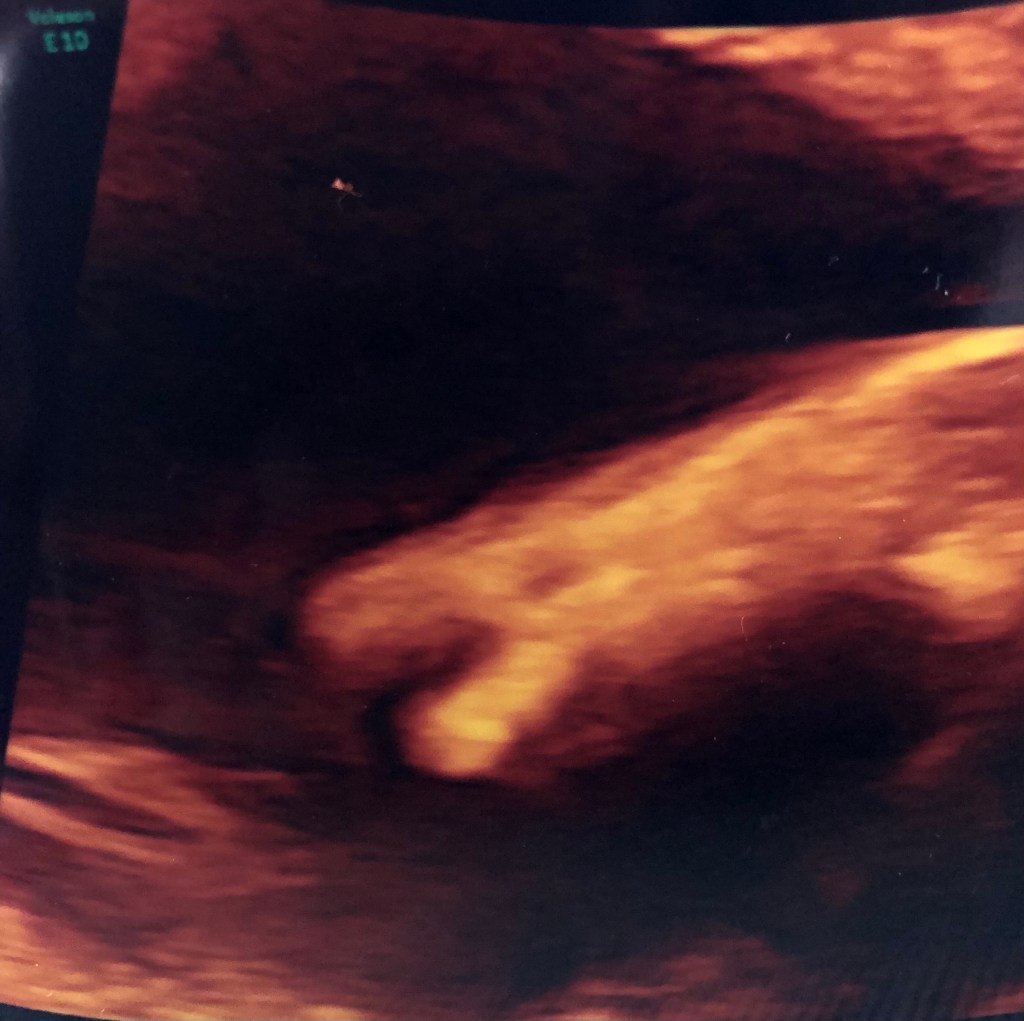

Da war er endlich.. der 03.06.2019, der Tag auf den wir alle gewartet haben. Es ist 11.30 Uhr, wir sitzen ganz entspannt im Wartebereich des Klinikums und Tobias streichelt meine mittlerweile doch recht gut gewachsene Murmel. Seine Worte: „Ich bin so gespannt was es wird, ach, egal.. Hauptsache alles gesund“, liegen mir heute noch in den Ohren. Endlich, wir wurden freundlich ins Zimmer gebeten. Voller Vorfreude machte ich den Bauch frei, schwang mich auf die Liege und wartete darauf, dass es los ging. Tobi saß wie damals bei Leni wieder an meiner Seite und griff meine Hand. Wir genossen die ersten Minuten. Der Arzt sagte nicht sehr viel und sah sich erst einmal alles an. „Sie wissen was es wird“, fragte er uns. „Ich sehe eindeutig die kleinen Eier“ fuhr er fort. Tobi‘s und meine Blicke trafen sich, wir konnten unser Glück kaum fassen. Ein kleiner Mann macht also unsere Familie komplett. Der Arzt untersuchte Herz und Organe, redete aber weiter nicht sehr viel. Nach einer kurzen Zeit sah er uns an und bat uns ein paar Treppen zu laufen.“ Ich kann das linke Ärmchen noch nicht so genau untersuchen, er versteckt es immer. Laufen sie ein wenig und kommen nach 10 min wieder“. Gesagt, getan.. Wer mich kennt, weiß, dass ich alles sofort meinen Eltern und den engsten Freunden mitteilen muss. Ich schickte per WhatsApp ein blaues Herz. Nach 10 Minuten fanden wir uns wieder im Wartebereich ein. Der Arzt bat uns noch kurz zu warten, er würde uns gleich hinein bitten. In der Zwischenzeit sah ich eine Frau im weißen Kittel mit Stöckelschuhen im gleichen Untersuchungsraum eintreten, indem wir 5 Minuten später auch wieder rein gebeten wurden. Ich legte mich wieder auf die Liege. Dieses Mal führte die Dame im weißen Kittel den Ultraschall durch. Die Haare streng nach hinten zu einem Dutt gebunden, ein ernster Blick und auch sie sprach nicht viel. Jedoch dauerte es nur ca. 1 Minute, bis sie dem Arzt zunickte, sich zu uns drehte und mit dem Satz: „Ihr Kind hat eine Fehlbildung an der oberen Extremität“ konfrontierte. Es wurde still, sehr still. Niemand sprach ein Wort. Ich starrte auf den Bildschirm. Meine Gefühlslage in dem Moment kann man schlecht in Worte fassen, ich empfand Angst, ich war unendlich traurig und gleichzeitig empfand ich Hass, Hass auf die Frau im weißen Kittel und den Stöckelschuhen. Wie kann man so etwas so unsensibel an werdende Eltern herantragen. Es war immer noch still im Raum. Tobi hielt meine Hand weiterhin fest, sein Gesicht veränderte sich schlagartig in Trauer. Plötzlich sagte der Arzt, dass er in diesem Moment gerne einen Seelsorger rufen würde. Tja und da war es passiert. Der 03.06.2019, der Tag an dem eine Welt für mich zusammenbrach. Total verstört fing ich an zu weinen, der Arzt brach die Feindiagnostik ab und begleitete uns in einen Nebenraum. Ich konnte mich kaum auf den Beinen halten, ich war müde, totmüde, wollte allein sein, dann wieder doch nicht, ich verlor vollkommen die Fassung.Mir riss der Boden unter den Füßen weg. Ja, ich möchte nichts beschönigen.. mir ging es richtig schlecht. Der Arzt versuchte noch zu erklären, dass er einen Termin in Leipzig veranlassen werde, bei einem Spezialisten, der genauer drauf sehen kann. Mir war alles egal, ich wollte einfach nur weinen. Tobi hielt sich wacker, er sah wie schlecht es mir ging. Auf dem Weg nach Hause beruhigte ich mich ein wenig, rief meine Eltern an und bat, dass Leni bei ihnen bleibt, denn so sollte unser Kind uns auf keinen Fall sehen. Mir war warm, und doch kalt, die Klimaanlage musste auf dieser Fahrt einiges aushalten. Mein Kopf war leer. Tobi und ich redeten auf der Heimfahrt kein Wort miteinander. Jeder starrte nur vor sich hin. An der Ampel sah ich, wie nun auch bei ihm kein Halten mehr war.. wir weinten beide, bitterlich! Er fuhr auf Nachtschicht, für ihn war es gut, er hätte nicht zu Hause bleiben können. Ich setzte mich auf die Couch und da saß ich. Es ist 18 Uhr.. ich bin alleine zu Hause, ich weine vor mich hin. Hilfe wird mir von Eltern/Schwiegereltern und engen Freunden angeboten. Doch ich will niemanden sehen. Ich möchte da einfach so sitzen, allein auf der Couch und einfach nur weinen..